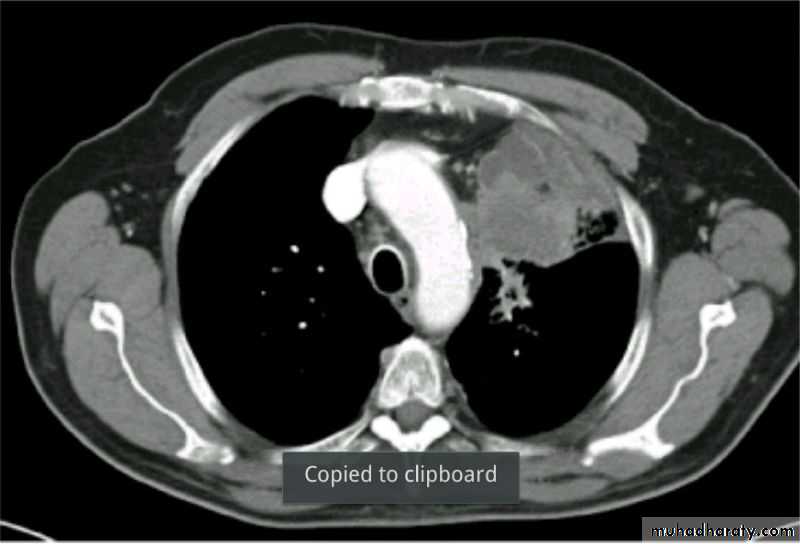

Patient with fever, rigor and dyspnea

Severe dyspnea with shock